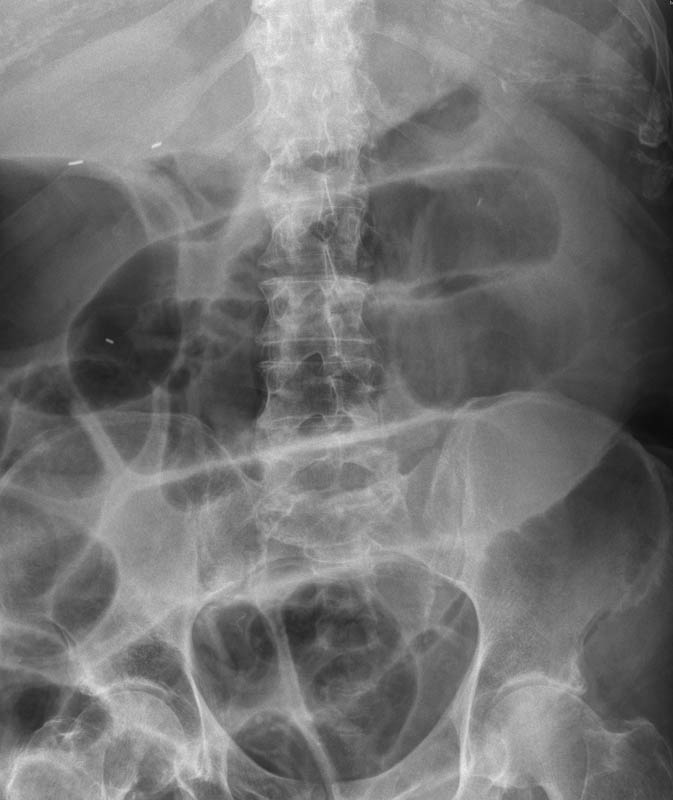

Diverticulosis de colon.

Diverticulosis de colon. Megacolon.

Dolico-megacolon.